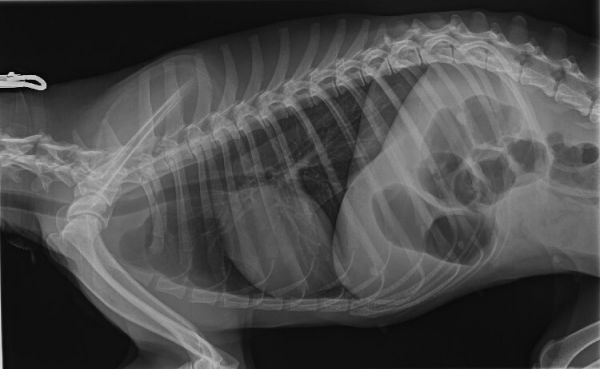

兽用数字化X射线摄影系统采用高频高压发生器和球管闭环控制,输出稳定,双核控制,用户可以对参数进行调整。